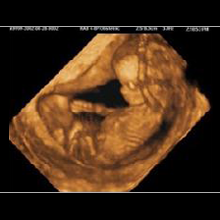

Eine ganz besondere Faszination bieten die neuen 3D/4D Ultraschallgeräte.

Die 3D-Sonografie erlaubt die einzigartige räumliche Darstellung des ungeborenen Kindes. In der 4D-Technik werden Bewegungsabläufe in nahezu fotorealistischer Weise in Echt-Zeit (Real-Time) mit bis zu 25 Bildern/sec. möglich- ein faszinierender Einblick in die Welt des Ungeborenen.

HIER EINE AUSWAHL VON 3D-ULRASCHALL-BILDERN:

Die digitale Verarbeitung ermöglicht die Rotation in jeder Richtung und die Anfertigung von Schnittbildern in jeder Ebene. Wir führen 3D/4D Ultraschalluntersuchungen im Rahmen unserer Wahlleistungen (IGeL) durch.

Wir beraten Sie gerne, bitte sprechen Sie uns an. 3D/4D-Ultraschall-Untersuchungen sind deutlich mehr als "Baby-TV".